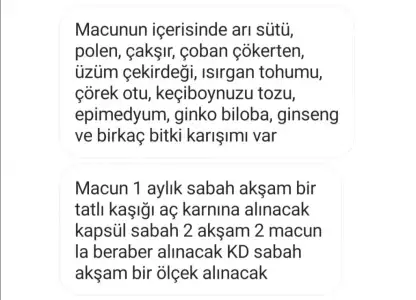

Oo çok pahalıymış canım eşin için sperm kalitesini yükselten vitaminler var aslında fiyatları da o kadar yüksek değilŞimdi sitede gezinirken okudum Çakşır suyunu siparıs verdım internetten eşime içirmeyi dusunuyotum bır arkadas macundan bahsetti fakat önerdıgı aktarcı 650 tl para istediinşallah yararlı olur... Oda dogru calısırken de gelıodu valla aklıma anıden sürekli müdürden izin alıp wc gidiyordum test yapmaya